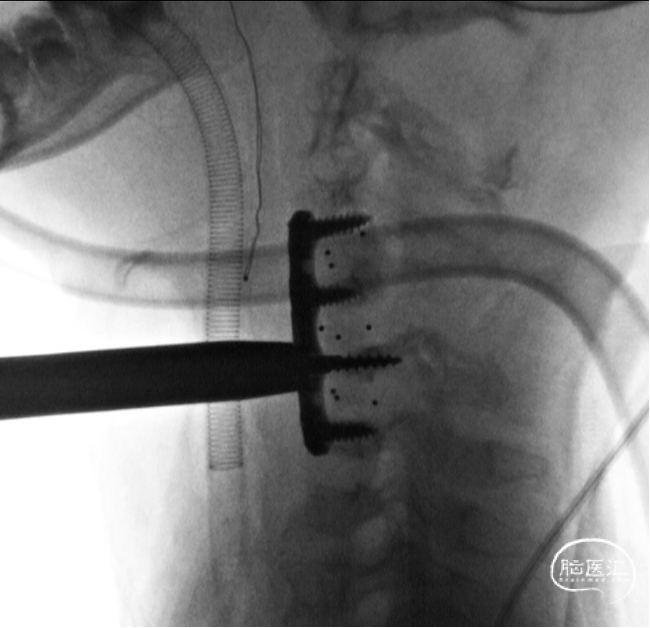

前路手术完成后,翻身行后路C2-C7置钉

C4及C5侧块无法置钉,双侧C5放置椎板钩增加把持力